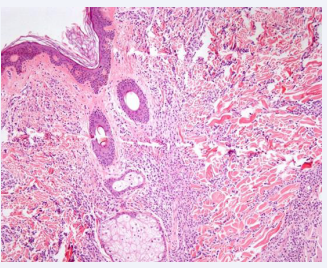

Figure 2: Normal epidermis, well-defined Grenz zone. The superficial and deep dermis is extensively infiltrated by neoplastic cells of hematolymphoid lineage, surrounding the cutaneous appendages. These cells vary in size, with some exhibiting plasmacytoid features extending into the subcutaneous tissue.

The skin biopsy revealed an epidermis with no significant changes, with a well-defined Grenz zone. At higher magnification, the superficial and deep dermis were extensively infiltrated by neoplastic cells of hematolymphoid lineage surrounding the cutaneous appendages. These cells varied in size, with some appearing plasmacytoid and extending into the subcutaneous tissue. Immunohistochemistry showed positivity for lysozyme, myeloperoxidase, Ki67, CD43, and CD68 (Figure 4).

Histological diagnosis of MS needs a high index of suspicion and may elude detection in the absence of AML history. In our case, the diagnosis was confirmed through pathological examination and immunophenotypic detection. [10] Notably, neoplastic infiltration, densely observed in the dermis and fat, exhibits a tendency to circumvent vessels and adnexa, sparing the papillary dermis (Grenz zone). Cytological appearance varies dependent on origin and cellular maturation degree. Immunohistochemistry (IHC), notably including CD68, MPO, CD43, CD3, CD20, and chloroacetate esterase, constitute pivotal diagnostic tools [3].